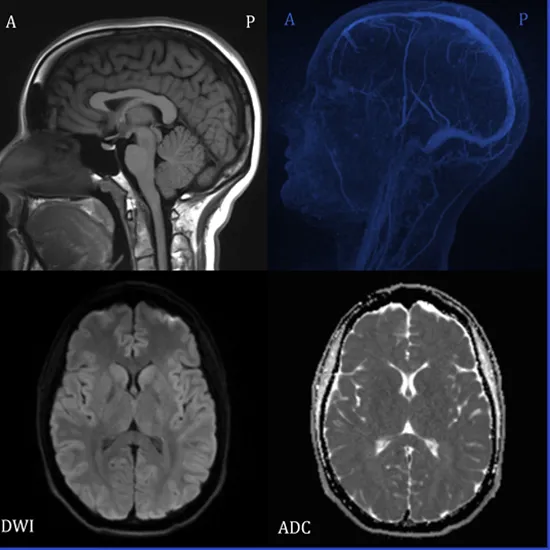

A brain MRI (magnetic resonance imaging) scan, also known as a head MRI, is a non-invasive procedure that produces very clear images of the structures inside your head, most notably your brain. To generate these detailed images, MRI employs a large magnet, radio waves, and a computer. It does not employ radiation.

MRI Brain test shows:

• Your brain

• Blood vessels that supply blood to your brain.

• Your facial bones and skull.

• Structures found in the inner ear.

• Your eyes and the tissues that support them, such as your optic nerves.

• Different nerves (large nerves in your head, called cranial nerves).

• Fat, bones, muscle, and connective tissue surround the soft tissues and skull-based structures.